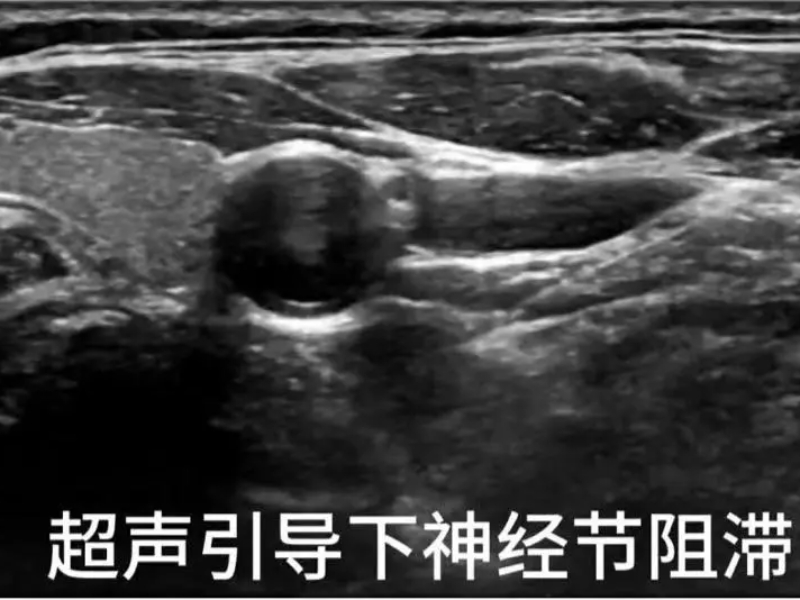

我院疼痛科的治疗优势

疼痛科在面瘫治疗方面具有独特的优势,采用中西医结合的方法,取得了显著的疗效。